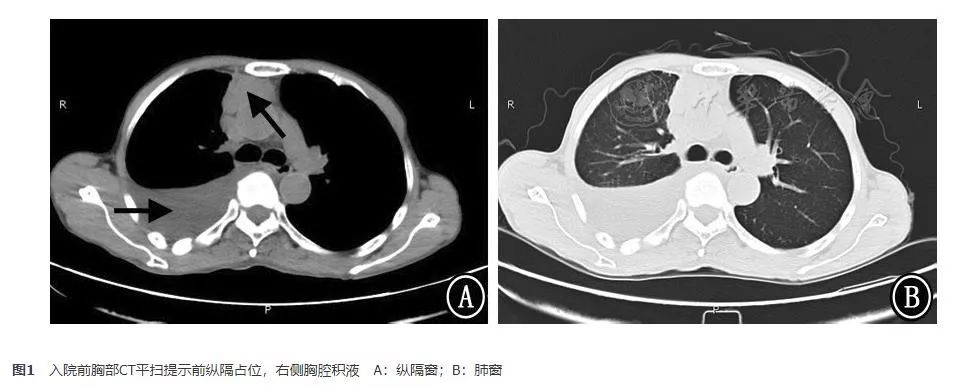

患者男,60岁。因"咳嗽、气短3周,加重2 d"于2017年11月17日入住我院呼吸内科。患者于入院前3周左右劳累后开始出现咳嗽,为干咳,伴有气短,无明显咳痰,无鼻塞、流涕等上呼吸道感染症状,无发热。患者未予重视,仅自行服用止咳糖浆治疗,症状未缓解。入院前2天,患者自觉症状加重,于上海交通大学医学院附属新华医院呼吸科门诊就诊,查胸部CT平扫(2017年11月15日)提示:前纵隔占位,右侧胸腔积液,伴右肺下叶不张(图1)。为进一步诊治,收治入院。否认药物食物过敏史、手术外伤史、传染病史。否认既往其他系统病史。有吸烟史40余年,每日10支。无特殊职业史。入院查体:血压120/80 mmHg(1 mmHg=0.133 kPa)。意识清楚,呼吸稍促。全身皮肤未见黄染,无瘀点、瘀斑。浅表淋巴结未触及肿大。左肺呼吸音稍粗,右下肺呼吸音减弱,两肺未闻及干湿啰音和胸膜摩擦音。心率126次/min,律齐。腹平软,无压痛、反跳痛及肌卫,肝脾肋下未触及。双下肢无水肿。生理反射存在,病理反射未引出。

图1 入院前胸部CT平扫提示前纵隔占位,右侧胸腔积液 A:纵隔窗;B:肺窗